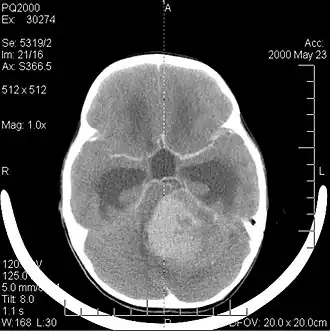

Beelddiagnose

Computertomografie (CT) en magnetische resonantiebeeldvorming (MRI) kunnen neoplasie in de hersenen effectief detecteren. MRI is gevoeliger dan CT voor het identificeren van laesies, maar heeft contra-indicaties voor patiënten met pacemakers, incompatibele prothesen, metalen clips en andere. CT blijft de voorkeursmethode om calcificaties in laesies of boterosie van het kalotje of de basis te detecteren. Het gebruik van contrastmiddelen, die gejodeerd zijn in het geval van CT en paramagnetisch (gadolinium) in het geval van MRI, maakt het verkrijgen van informatie over de vascularisatie en integriteit van de bloed-hersenbarrière mogelijk, een betere definitie van de tumorachtige tumor vergeleken tot het omringende oedeem en het genereren van hypothesen over de mate van maligniteit. Het radiologisch onderzoek maakt ook een beoordeling mogelijk van de mechanische effecten en de daaruit voortvloeiende veranderingen in hersenstructuren als gevolg van de tumor, zoals hydrocefalus en hernia's, waarvan de effecten fataal kunnen zijn. Ten slotte kan deze diagnostiek, ter voorbereiding op een operatie, worden gebruikt om de locatie van de laesie of de infiltratie van de tumor in vitale delen van de hersenen te bepalen. Voor dit doel is MRI efficiënter dan CT omdat het driedimensionale beelden kan opleveren. Diagnostische radiologische beeldvormingshulpmiddelen benadrukken de verandering in neoplastisch weefsel in vergelijking met normaal hersenparenchym (door veranderingen in elektronisch afgebeelde weefseldichtheid op CT en signaalintensiteit op MRI). Zoals de meeste pathologische weefsels zijn tumoren ook herkenbaar aan een verhoogde ophoping van intracellulair water. In het computertomogram lijken ze hypodens, dwz met een lagere dichtheid dan het hersenparenchym, in het kernmagnetische resonantietomogram met spin-roosterrelaxatie hypointenseen in spin-spin ontspanning evenals proton weging (PD) hyperintens.

Computertomografie van de hersenen toont typisch een weefselmassa die door beide contrasten kan worden versterkt. Op CT lijken laaggradige gliomen gewoonlijk isodense aan het normale parenchym en vertonen daarom mogelijk geen contrastversterking. Evenzo zijn laesies in de achterste schedelgroeve moeilijk te identificeren op CT. Bijgevolg zijn de resultaten van een dergelijke tomografie alleen niet altijd voldoende voor diagnostische doeleinden. In twijfelgevallen is het gebruik van de meer gevoelige magnetische resonantiebeeldvorming essentieel.